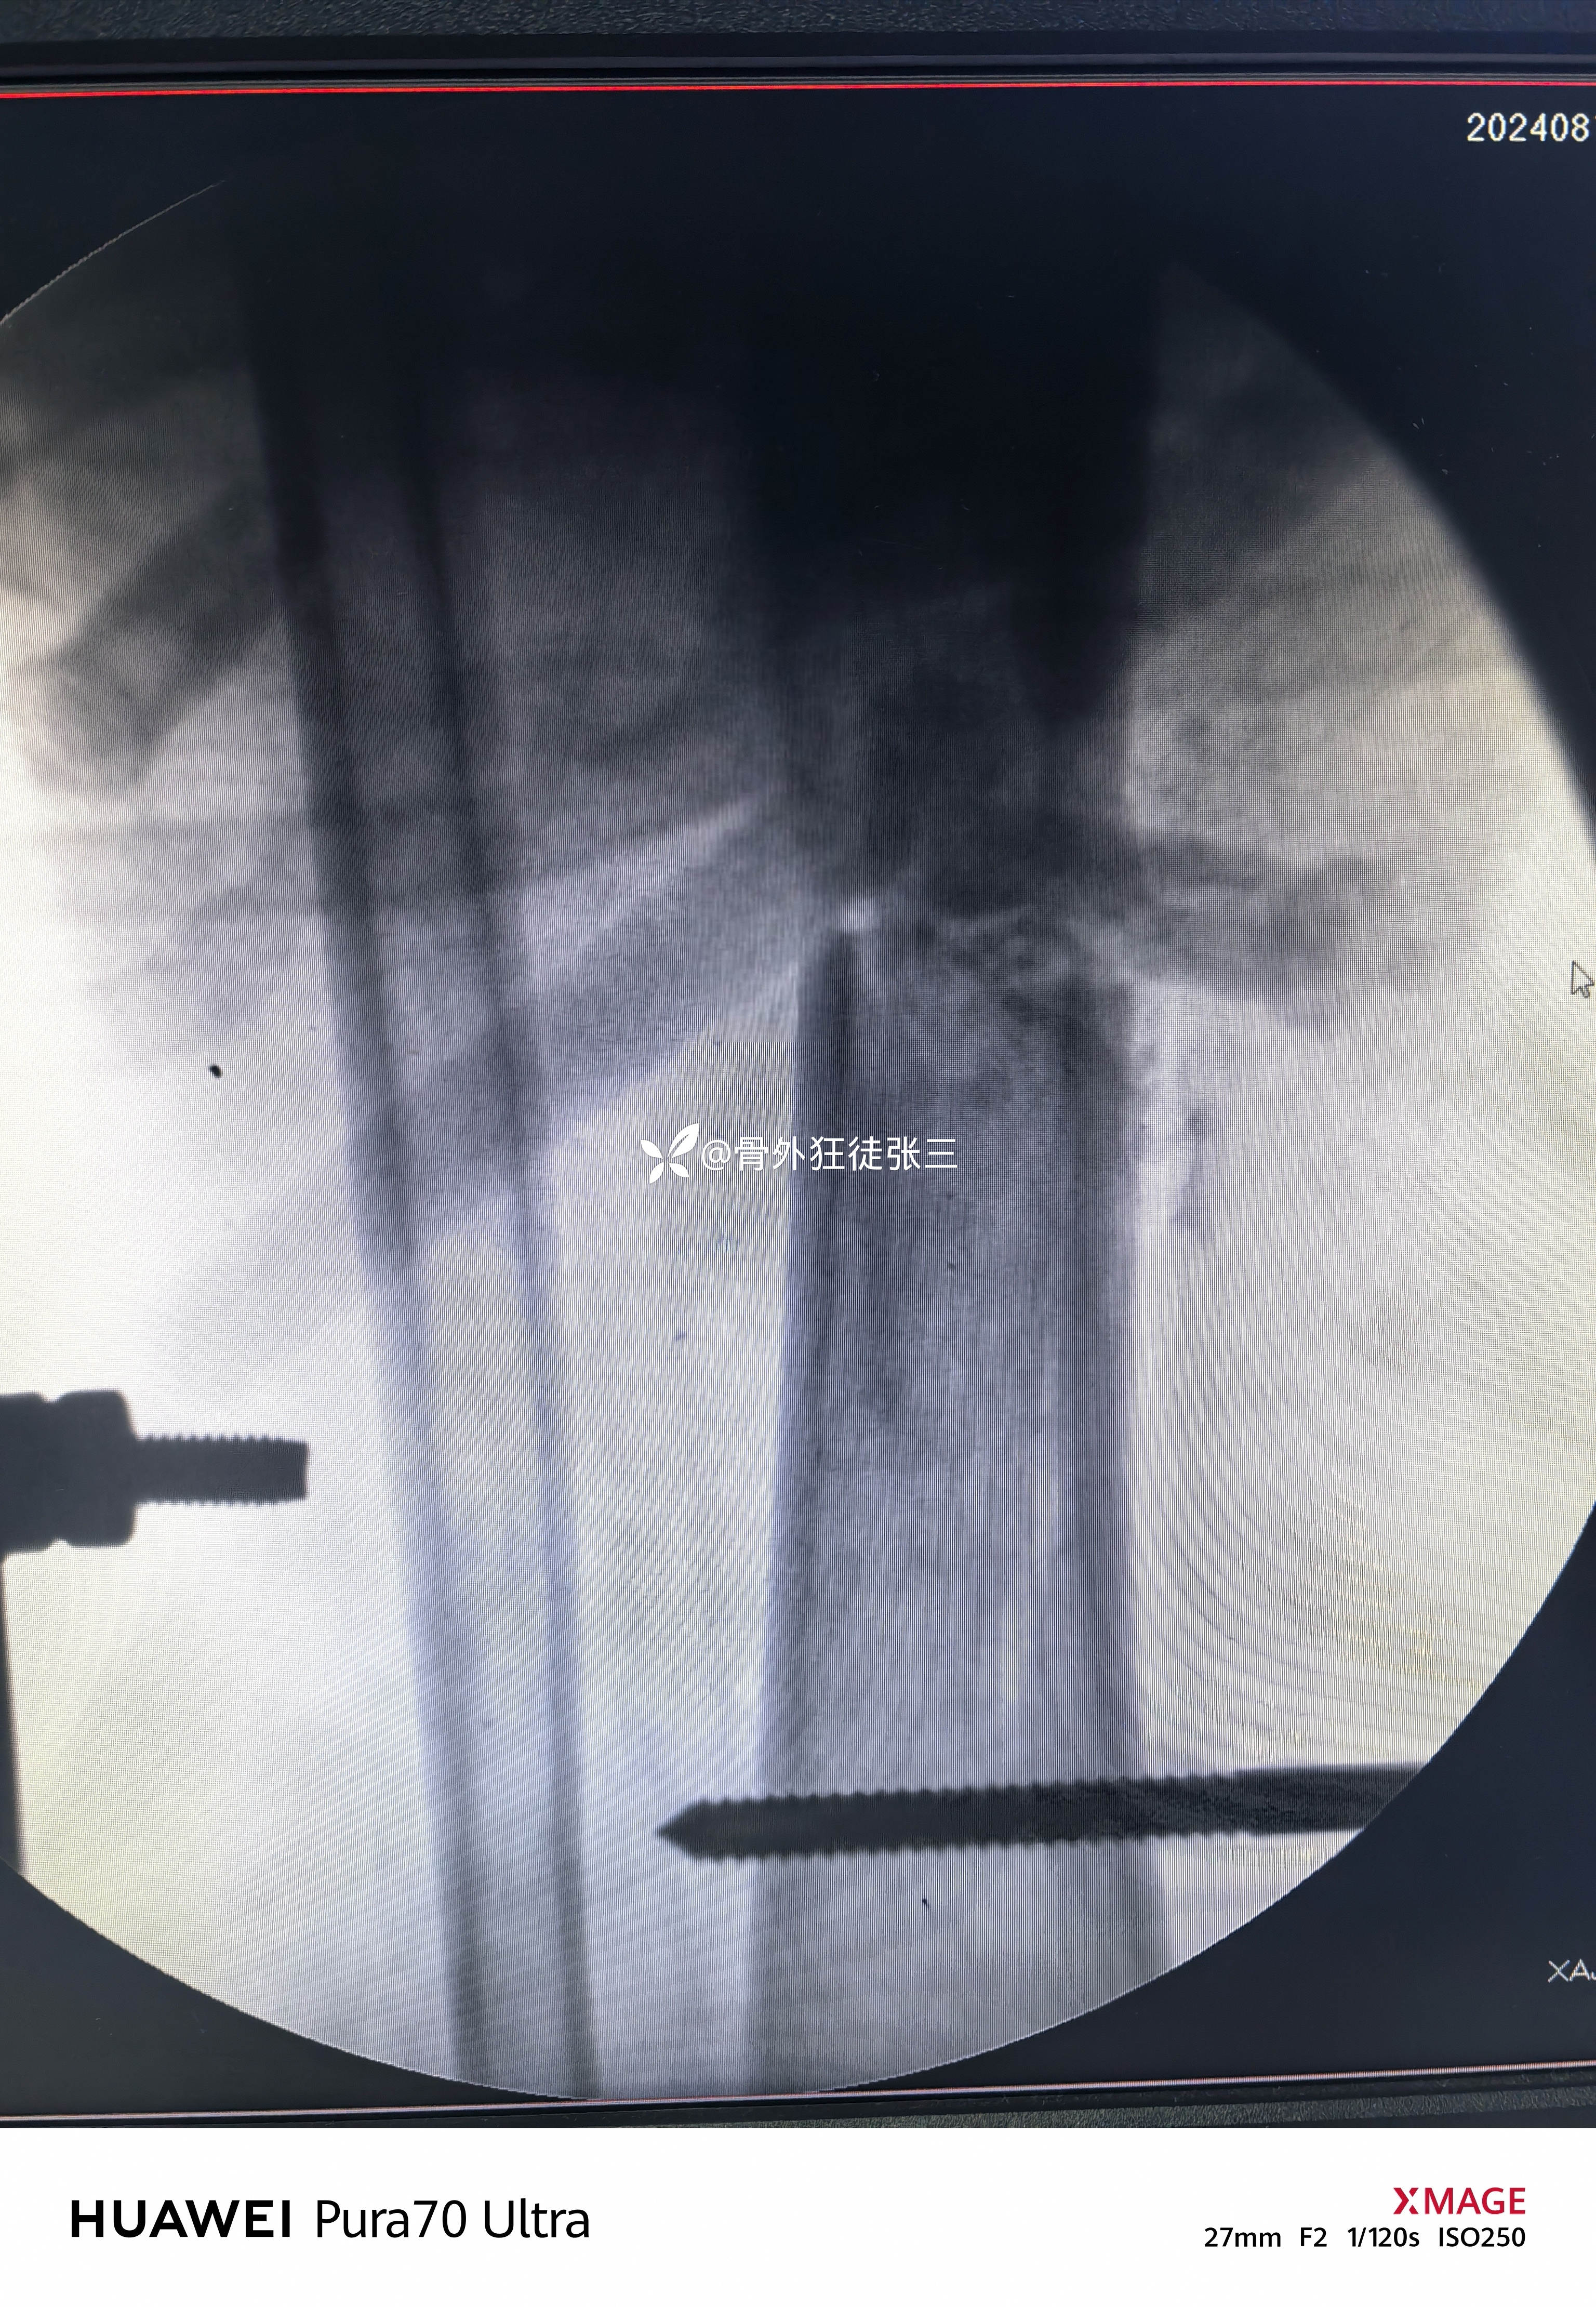

左胫骨平台骨折

平台准备终极固定

复位后给予克氏针固定

1,平台可否克氏针终极固定?